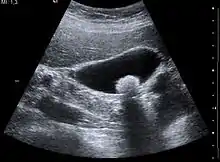

تتكون الحصوات الصفراوية عندما تَتَشبع العصارة الصفراوية، وغالبًا ما تكون إما مع الكولسترول أو البيليروبين.[6] مُعظم الحصوات الصفراوية لا تُسبب أعراضًا، حيثُ تبقى هذه الحصوات إما في المرارة أو تمر عبر الجهاز الصفراوي.[8] عندما تظهر الأعراض، فإنَّ ألمًا مغصيًا شديدًا عادةً ما يحدثُ في الجزء العلوي الأيمن من البطن.[6] قد يحدث التهابٌ في حال سدَّت الحصوة المرارة، أما إذا استقرت الحصوة في الجهاز الصفراوي، فإنهُ قد يحدث يرقان، وإذا سدت قناة البنكرياس فقد يحدث التهاب في البنكرياس.[8] تُشخص الحصوات الصفراوية باستخدام الموجات فوق الصوتية.[6] عند حدوث أعراض الحصوات الصفراوية، فإنه عادةً ما يتم التعامل معها بالانتظار حتى تمُر طبيعيًا،[8] ولكن نظرًا لاحتمال الإصابة المتكررة بالحصوات، فإنها غالبًا ما تُعالج بالإزالة الجراحية للمرارة،[8] ويُمكن أيضًا استعمال بعض الأدوية مثل حمض يوروديوكسي كوليك الذي يعمل على إذابة الحصوات. يمكن أيضًا استعمال تفتيت الحصيات، وهو عبارة عن إجراء يُستخدم لتفتيت الحصوات.[8]

عادةً ما يكون التصوير بالموجات فوق الصوتية أولَ فحصٍ تصويريٍ طبيٍ يُنفذُ مع أمراض المرارة مثل الشك بوجود حصواتٍ صفراوية.[8] من طُرق التصوير الأُخرى التصوير بالأشعة السينية للبطن أو التصوير المقطعي المحوسب، حيثُ قد تستخدم لفحص المرارة والأعضاء المحيطة بها.[8] يُمكن أيضًا استعمال خياراتٍ تصويرية أُخرى مثل تصوير البنكرياس والأوعية الصفراوية بالرنين المغناطيسي (MRCP) وتصوير البنكرياس والأقنية الصفراوية بالتنظير الباطني بالطريق الراجع (ERCP) وتصوير الأوعية الصفراوية بطريق الجلد أو أثناء العملية.[8] التصوير الومضاني الصفراوي هو تصويرٌ نووي يُستعمل لتقييم حالةِ المرارة.[45]